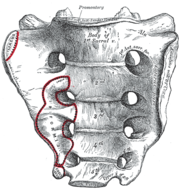

العجز، السطح الحوضي. | |

في البشر، العجز sacrum ( []ˈsækrəm[] أو []ˈseɪkrəm[]; مفرده: sacrums أو sacra)، هي عظام كبيرة، مثلثة الشكل، تقع على قاعدة العمود الفقري وعلى الجزء العلوي، الخلفي لتجويف الحوض، حيث تكون مغروزة مثل الوتد بين عظام الورك. الجزء العلوي منها تتصل بالفقرة القطنية، والجزء السفلي منها متصلة بالعصعص. عادة، يبدأ العجز كفقرة خامسة غير ملتحمة تبدأ بالالتحام في عمر 16-18 سنة وعادة ما يكتمل التحامها كعظمة واحدة في الرابعة والثلاثين.